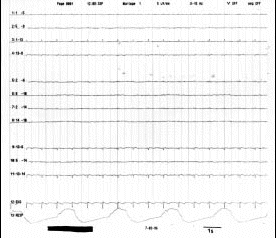

Figura 10.- Trazado electroencefalográfico donde se observa ausencia de actividad bioeléctrica. La única actividad observable es la del electrocardiograma.